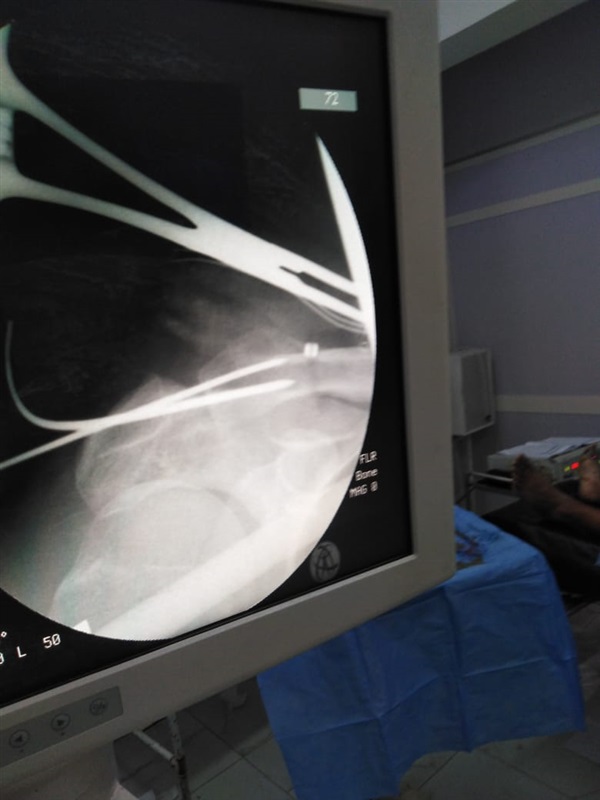

نجاح اول عملية تثبيت خلع بمفصل الكتف بتقنية جديدة بمستشفى دكرنس العام

اعلن الدكتور سعد مكي وكيل وزارة الصحة بالدقهلية عن نجاح فريق طبي بإجراء اول عملية تثبيت خلع بمفصل الكتف بتقنية جديده بمستشفى دكرنس العام لمريض يبلغ من العمر 40 عاما.

وأكد مكي ان استخدام التقنية الجديده، تقلل من آلام ما بعد الجراحة لدى المريض، وتحقق التعافي السريع وهي أفضل من الناحية التجميلية، كما أنها لا تستدعي إجراء عملية أخرى لإزالة الشرائح والمسامير المعدنيه.